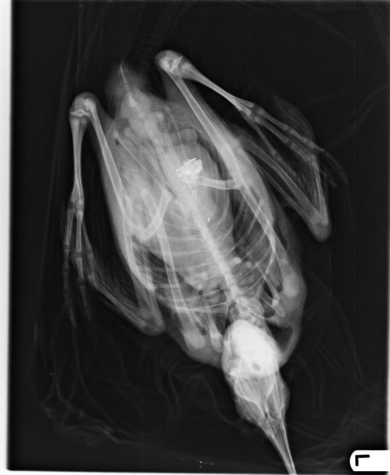

An X-ray on Monday revealed a sinker and hook inside the chick, and its lead levels had tripled over the weekend. Once lead is swallowed and in a loon’s gizzard, it dissolves into their bloodstream, leading to lead poisoning. Affected loons can’t fly, swim in uneven circles, and experience tremors. By the time such symptoms of severe lead poisoning appear, it cannot be cured and the bird typically dies in about two weeks.

Despite the high possibility that this loon chick wouldn’t survive, every effort was made to save the bird’s life. The chick was transferred to the Center for Wildlife in York, ME, where it was put under anesthesia and its gizzard was lavaged. It took two attempts over two days to wash the lead sinker out, after which the chick underwent a treatment for lead poisoning called chelation, using a medicine that binds to lead and flushes it out through urine. This treatment only works if the lead was recently ingested. This was also the first time that this procedure was performed on a Vermont loon. In most cases, it’s too late for this lead poisoning treatment by the time it’s clear that the bird is in trouble—displaying beaching behavior like this chick when it was found.